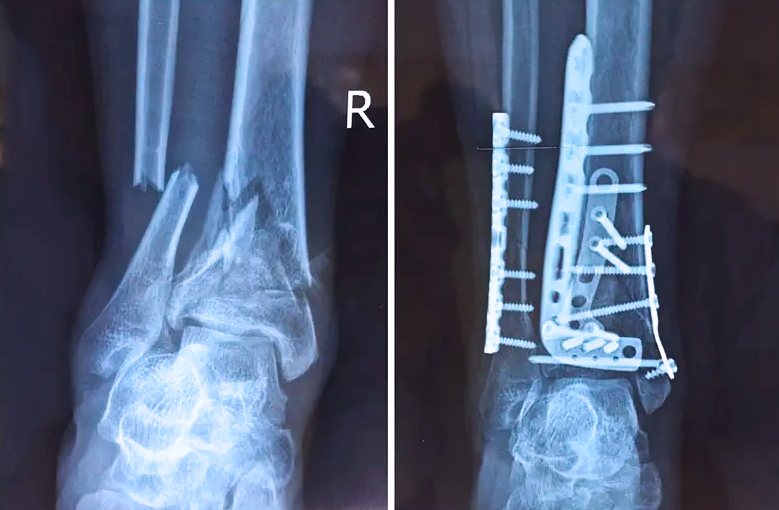

踝關(guān)節(jié)是人體中負(fù)重較大的關(guān)節(jié),也是活動度較大的地方,所以對于足踝部位的關(guān)節(jié)內(nèi)骨折,我們更需要做到“解剖復(fù)位”。對于這種關(guān)節(jié)內(nèi)的骨折,尤其是踝關(guān)節(jié)內(nèi)部的骨折,不僅需要進(jìn)行X影像平片正側(cè)位的拍攝,由于在二維影像上無法判斷關(guān)節(jié)面的受損情況,往往還需要進(jìn)行三維影像的檢查。

在術(shù)前,我們需要做三維掃描的CT檢查,我們必須要有CT的片子,還要有三維的重建。

在術(shù)中,我們怎么去判斷關(guān)節(jié)面平不平整呢?常規(guī)的正側(cè)位影像是不能判斷的。有些醫(yī)生為了準(zhǔn)確的判斷,可能會選擇做開放性的手術(shù),把關(guān)節(jié)暴露出來,在眼睛的直視下判斷關(guān)節(jié)面平不平整。但是關(guān)節(jié)全部打開,無疑增加了病人的創(chuàng)傷,而且增加了患者的恢復(fù)時間。所以如果在術(shù)中我們有三維影像的支持,對醫(yī)生做手術(shù)而言就會事半功倍,而且能夠大大的增加手術(shù)準(zhǔn)確度,增加患者術(shù)后的預(yù)后。所以在術(shù)中有三維影像的支持是非常必要的!